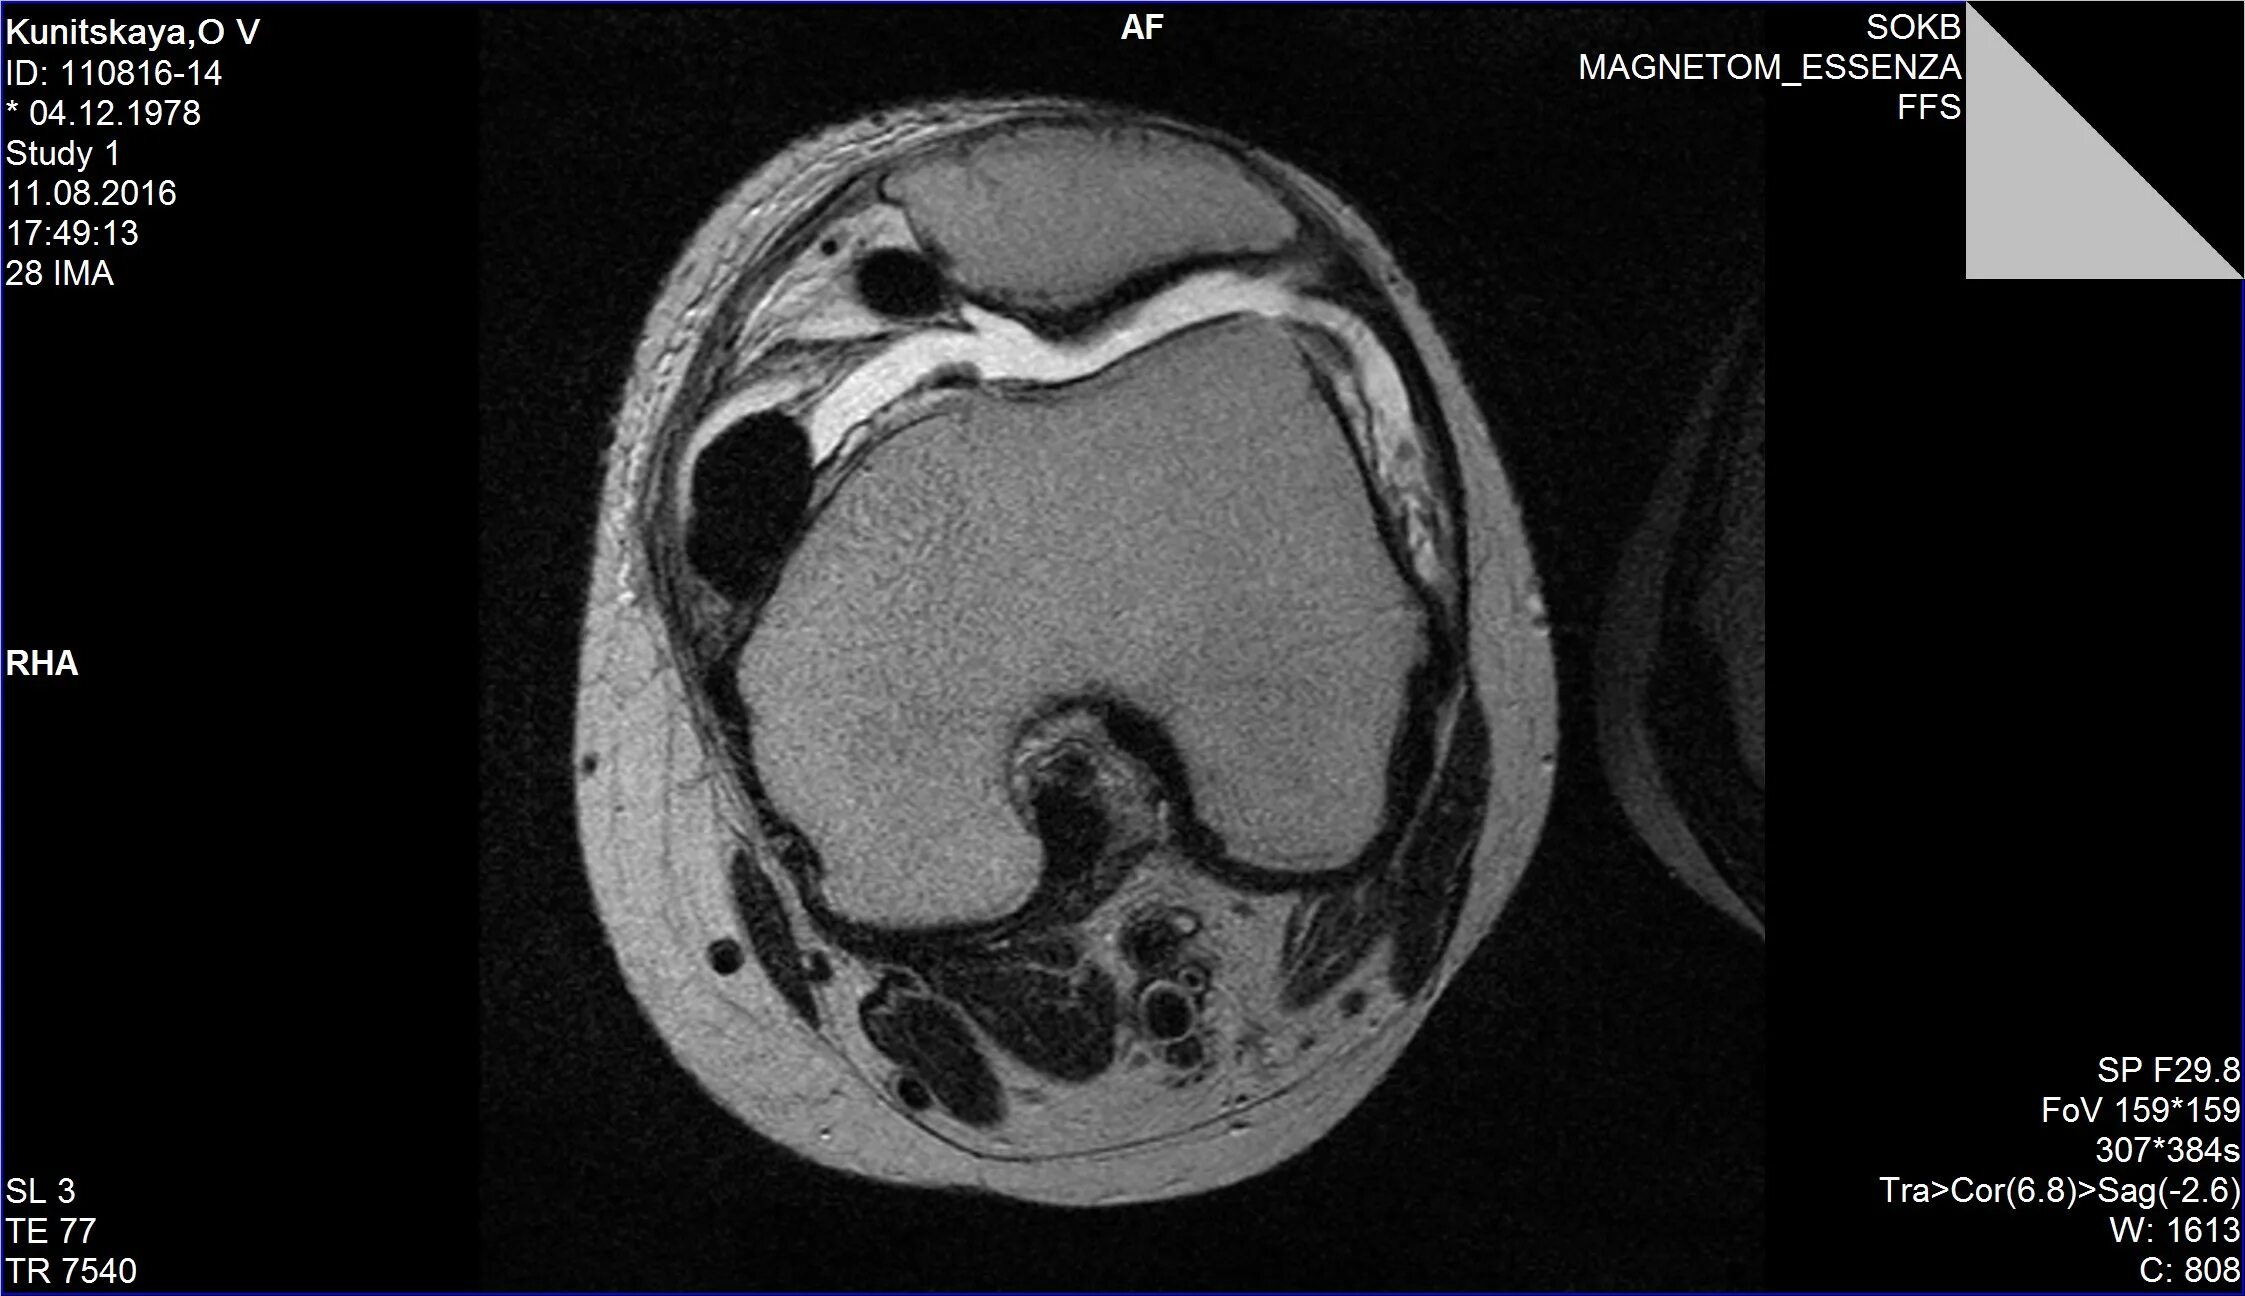

Пигментный виллонодулярный синовит